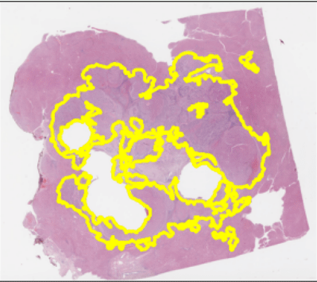

Inverse Problems in Digital Pathology